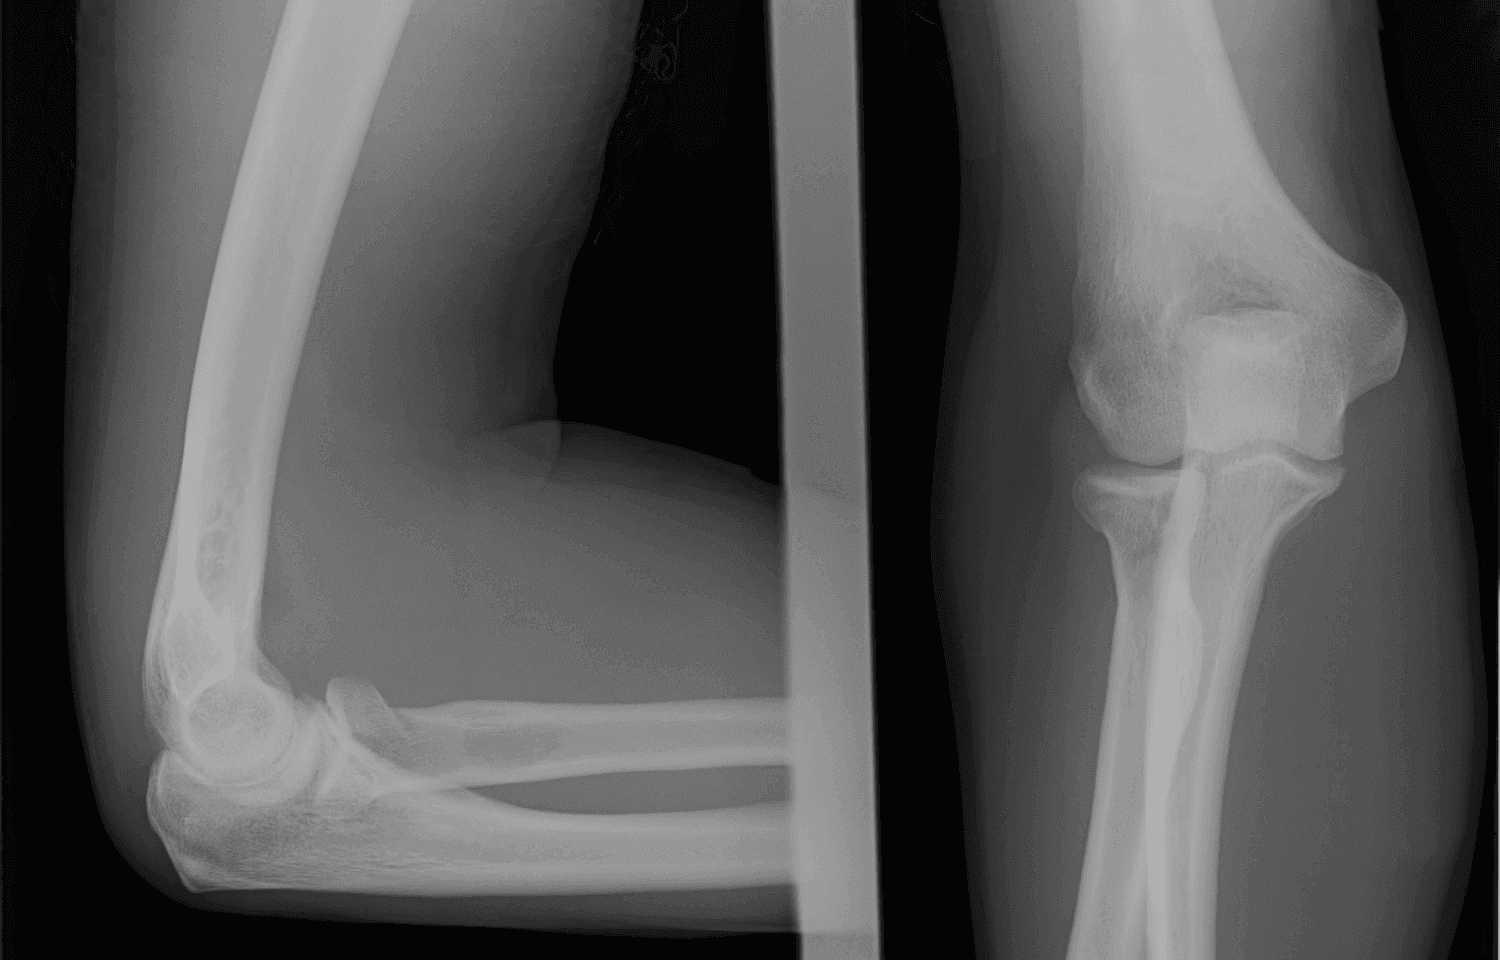

Röntgen görüntüleri, kemik ve eklem yapılarının detaylı incelenmesini sağlayarak bu süreçte kritik bir rol oynar. Röntgen, basit ve hızlı uygulanabilir bir görüntüleme yöntemi olarak birçok alanda değerlendirilir.

Röntgen Kullanım Alanları:

- Kırık ve çatlakların teşhisi

- Eklem sorunlarının tanımlanması

- Karmaşık yaralanmaların analizi

Röntgen görüntülerinin doğru okunması, tedavi planlamasında hataları en aza indirir ve uygun cerrahi veya konservatif tedavi yöntemlerinin belirlenmesini sağlar.